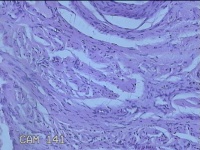

宫颈2点、10点组织

性别

女

年龄

21岁

临床诊断

人乳头瘤病毒感染

一般病史

发现人乳头瘤病毒5个月。

标本名称

大体所见

1.“宫颈2点组织”:灰白粉红色组织0.8x0.5x0.2cm一块。 2.“宫颈10点组织”:灰白暗红色组织0.8x0.6x0.3cm一块。